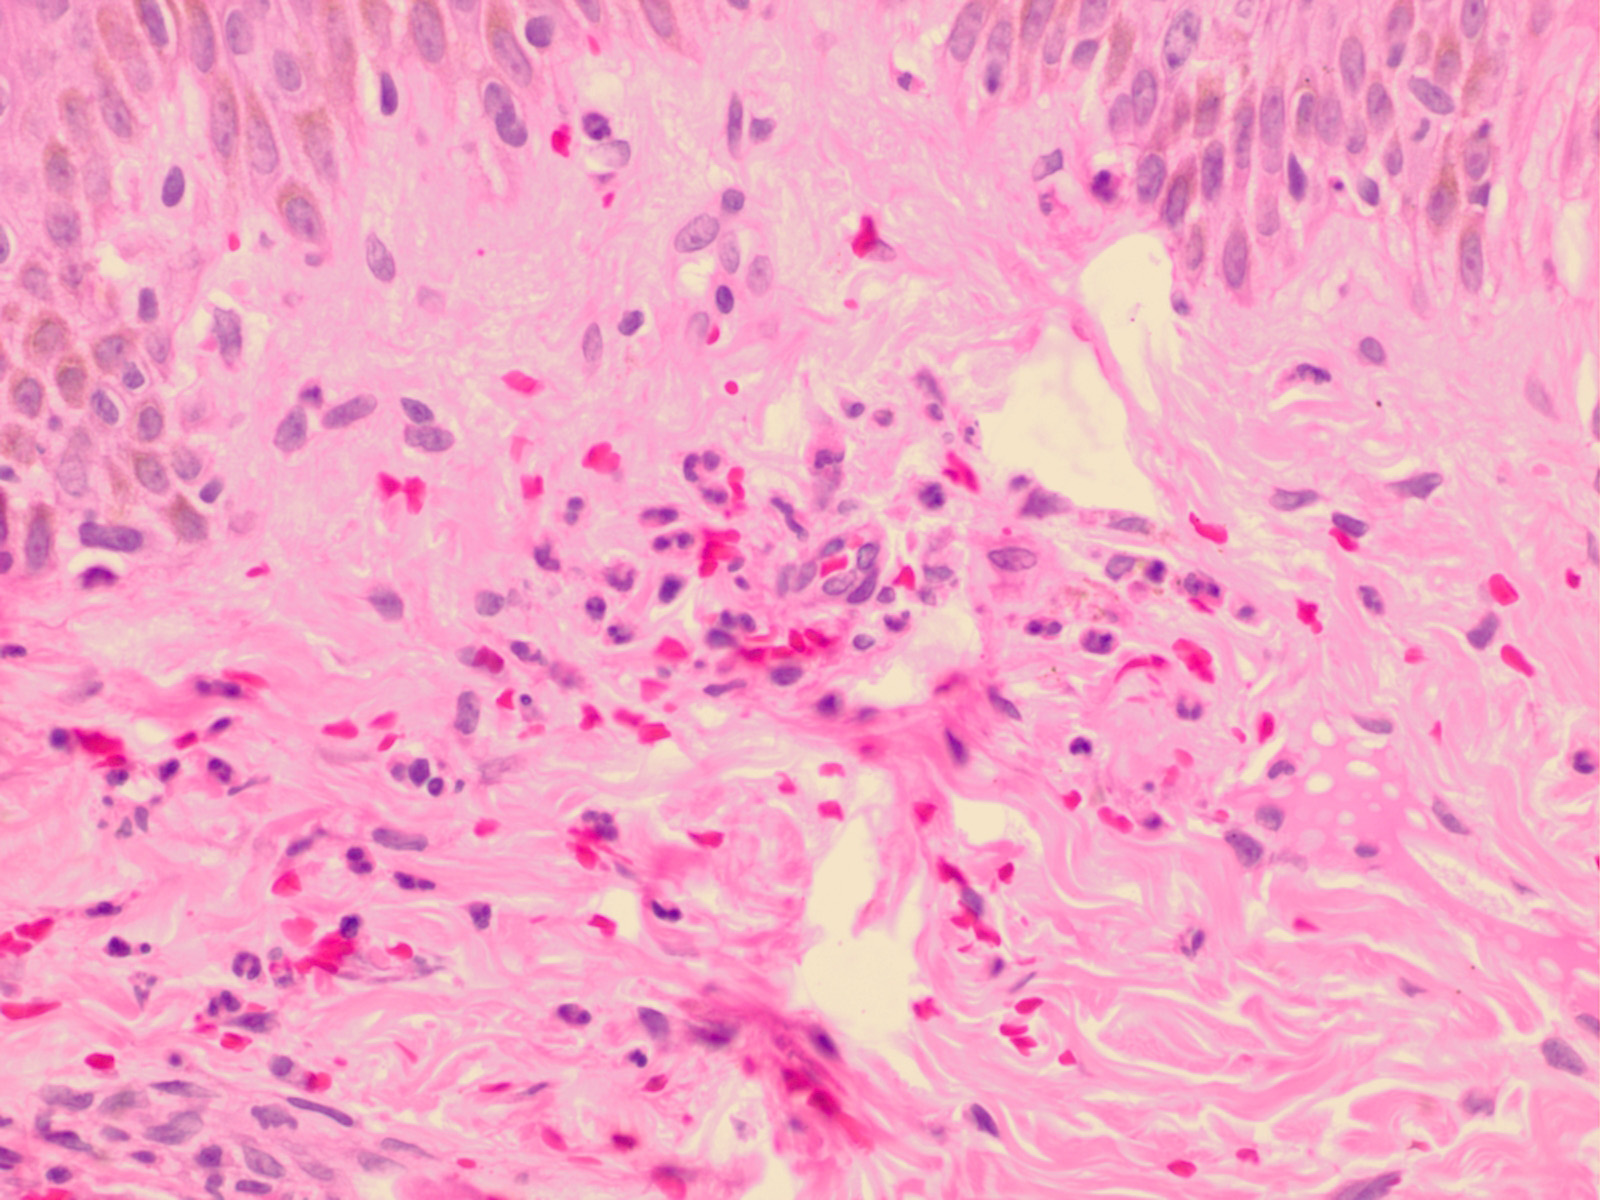

Septic vasculitis = التهاب الاوعية الانتاني